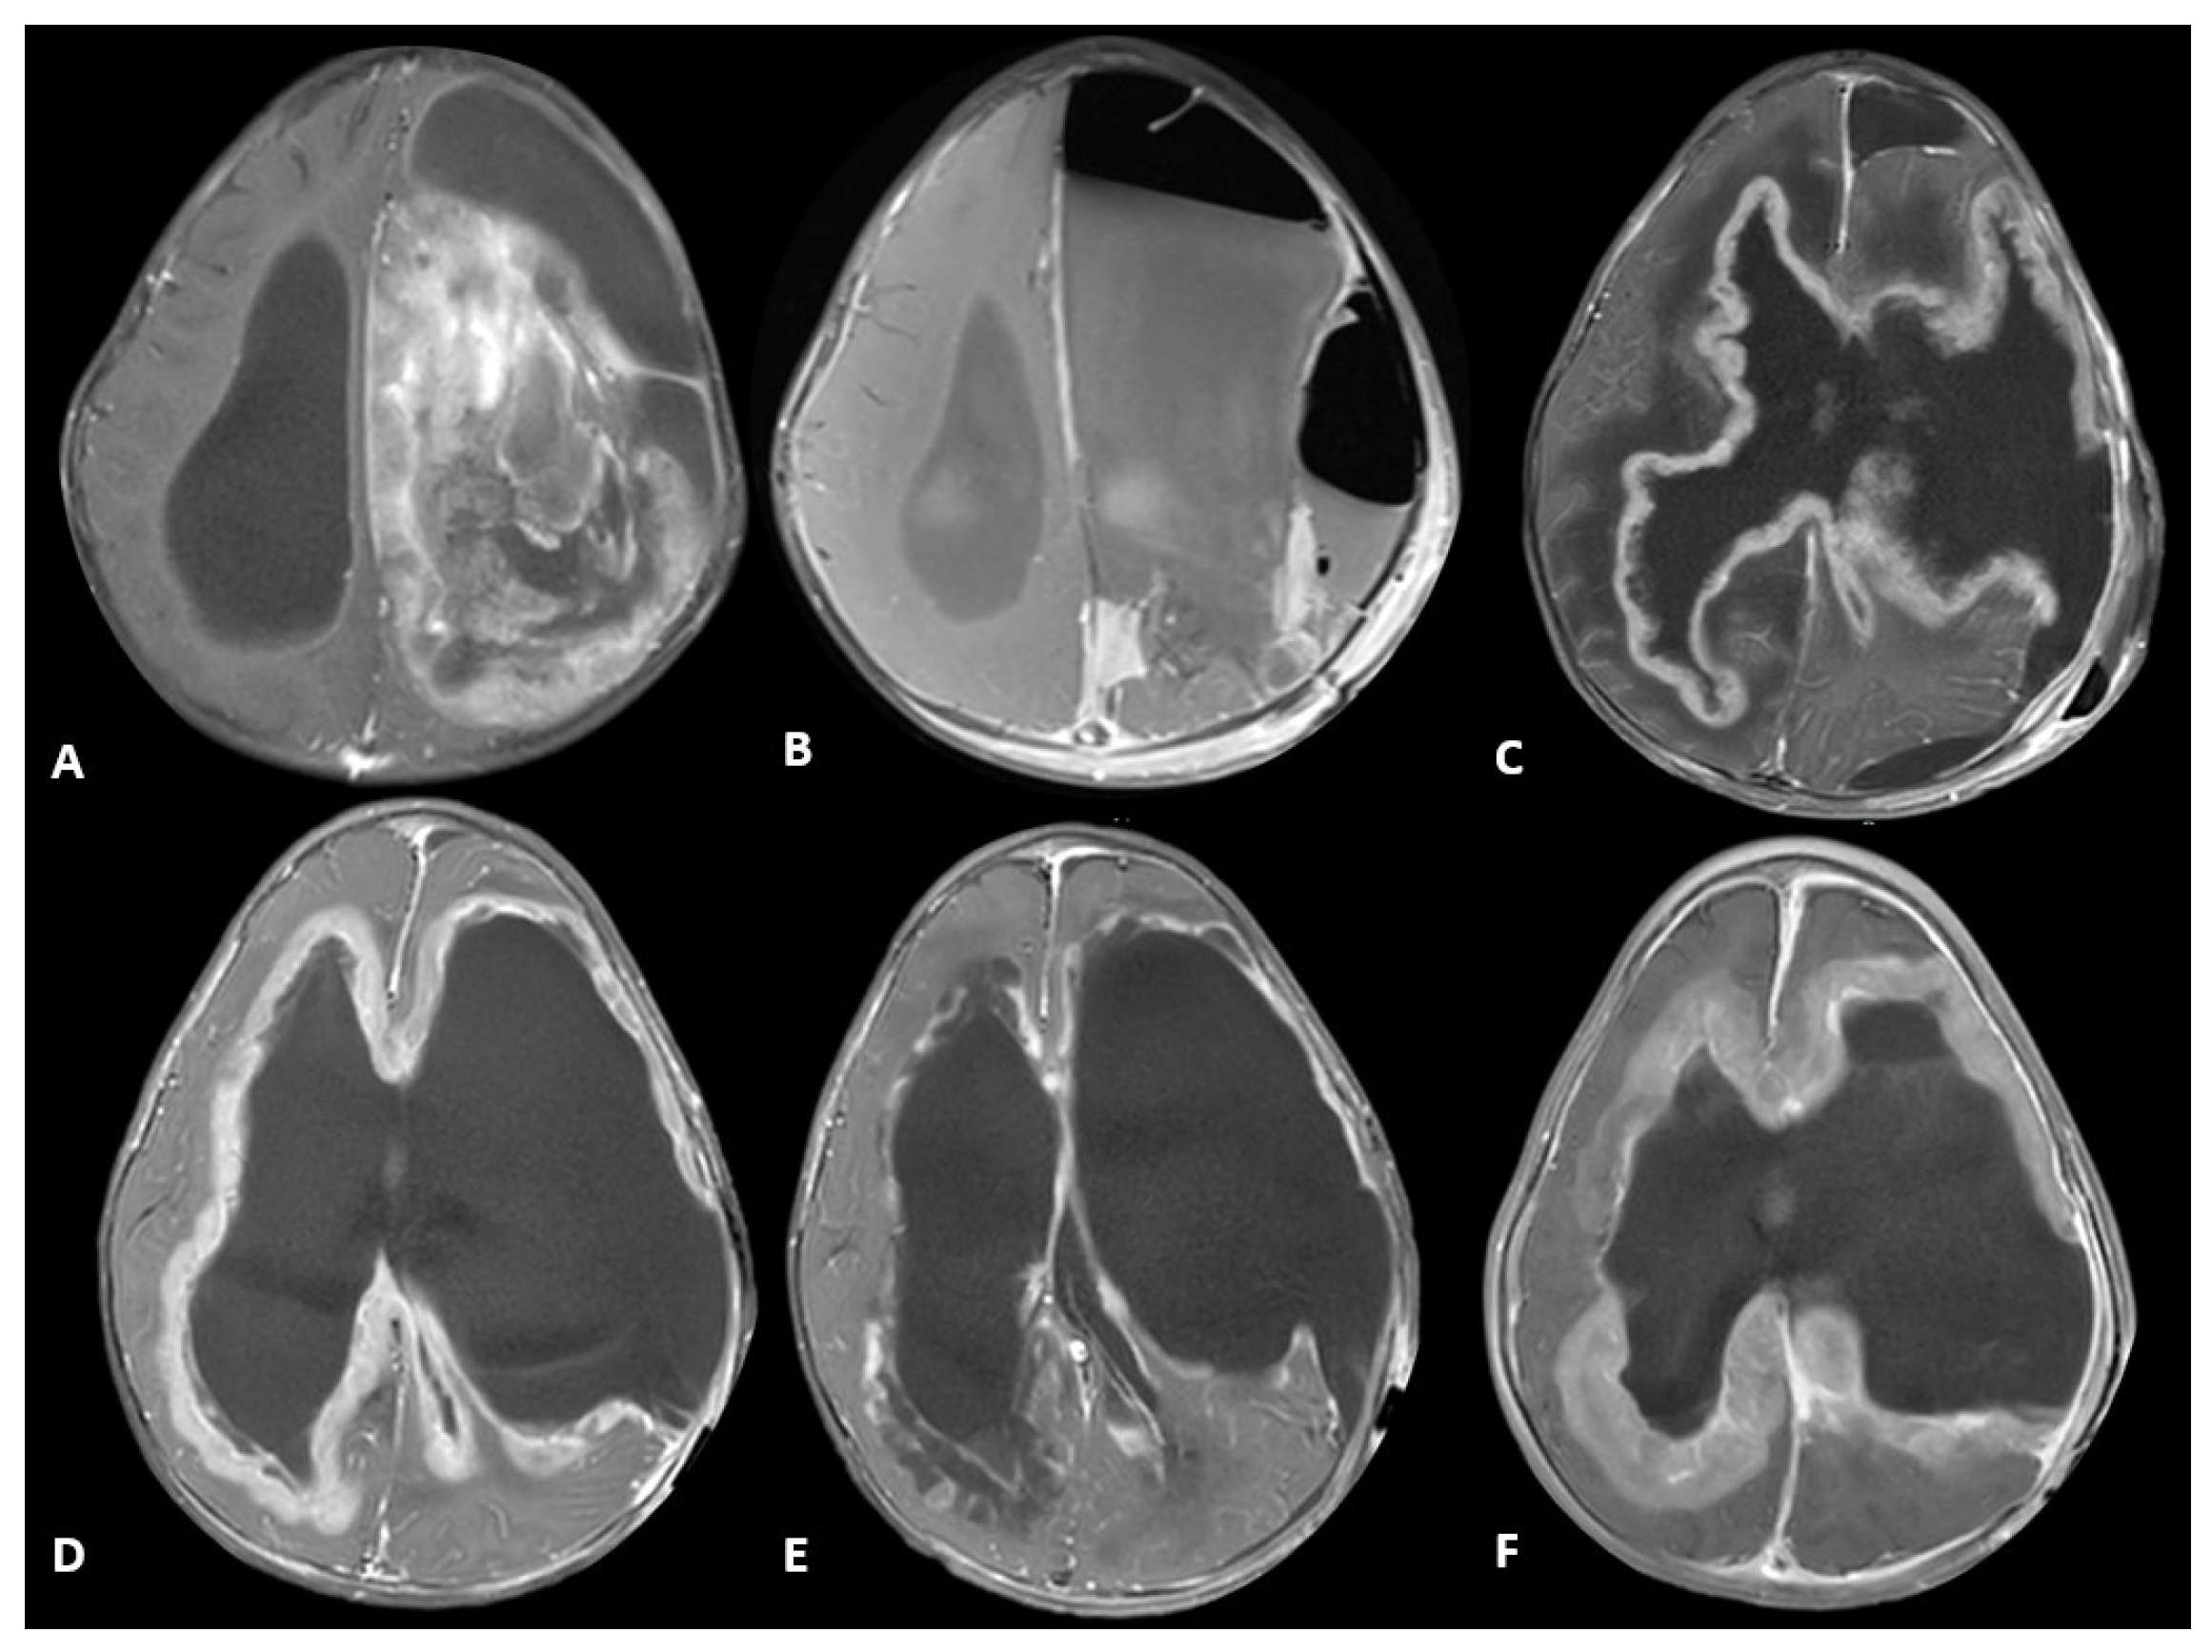

| Patient 1 | Diagnostic | -Brisk mitotic activity -Gliosis in myxoid background -Vimentin positive -olig2 positive -S-100 positive | -CLIP2-MET fusion -CHEK2 frameshift alteration -CDKN2A, CDKN2B, MTAP loss | Infant-type Hemispheric Glioma | Infant-type Hemispheric Glioma, WHO-CNS Grade 4 | Systemic chemotherapy: Cyclophosphamide, Vincristine, Cisplatinum and Etoposide (2 cycles) Targeted agent: Cabozantinib |

| Patient 2 | Diagnostic | -Brisk mitotic activity -INI1 retained -P53 diffusely expressed -olig2 positive | -MBOAT2-ALK fusion -TP53 loss -MYCN copy gain | Diffuse Pediatric-type High-Grade Glioma, MYCN subtype | Diffuse Pediatric-type High-Grade Glioma, H3-wild-type and IDH-wild-type, CNS WHO Grade 4 | Radiotherapy with concurrent Temozolomide Targeted agent: Lorlatinib |

| Relapse | Similar to diagnostic sample, with olig2 loss | -MET copy gain -MBOAT2-ALK fusion -TP53 loss -MYCN copy gain | Diffuse Pediatric-type High-Grade Glioma, MYCN subtype | Diffuse Pediatric-type High-Grade Glioma, H3-wild-type and IDH-wild-type, CNS WHO Grade 4 | Target agents: Lorlatinib and Cabozantinib |